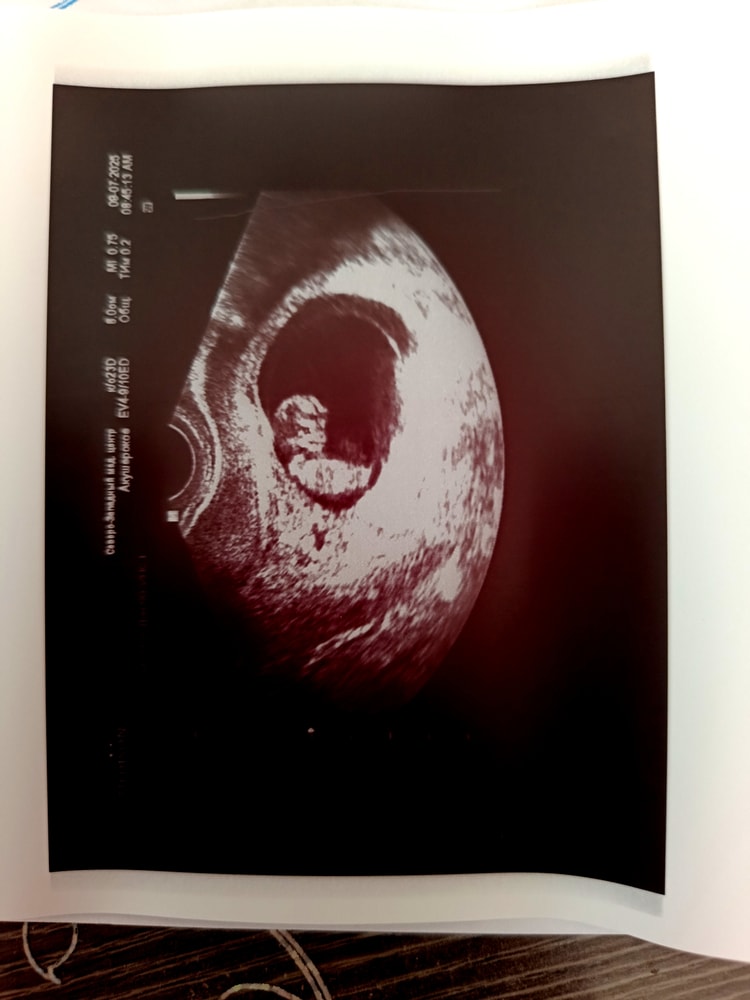

Мои 9 недель, вот😁Изображение

Вероника, ну, это ракурс при котором не видно отчетливо ☺️ а так у них там уже всё есть и видно хорошо

Svoya, я там умудрилась пол рассмотреть, слева голова и рот открыт, справа пуповина, а над ней бугорок идет вниз😂😂😂я говорю мужу, у нас девочка😂 потом в 15 нед действительно сказали, что девочка